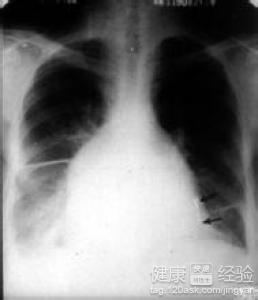

1該病的發病原因尚未明確,通常在臨床方面患者的心室會出了不對稱的肥厚跡象,並且侵及室間隔,心室內腔變小,左心室血液充盈受阻,左心室舒張期順應性下降。根據左心室流出道有無梗阻分為梗阻性及非梗阻性肥厚型心肌病。